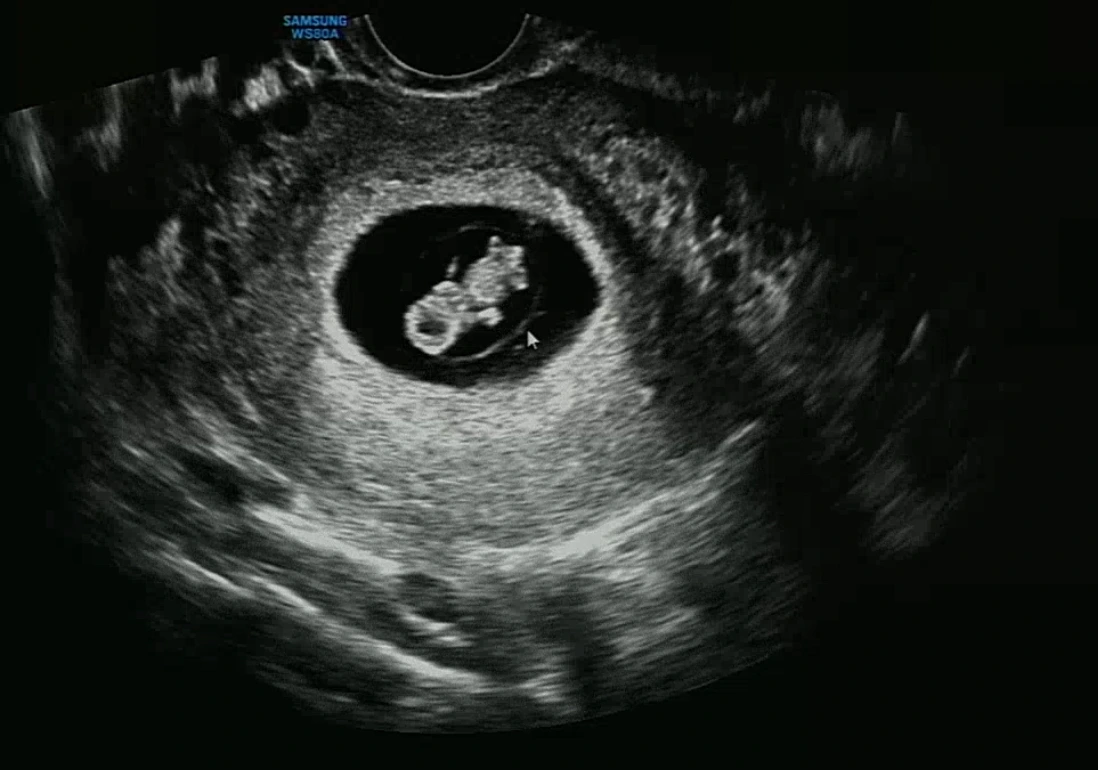

"아가 심장소리예요."

임신했다는 걸 확신하자마자 만난 너의 모습. 반가워! 그리고 미안해.

쿵쿵쿵쿵, 쿵쿵쿵쿵. 내 귀에 너무나 우렁차게 들리는 미약하지만 확실한 심장 소리.